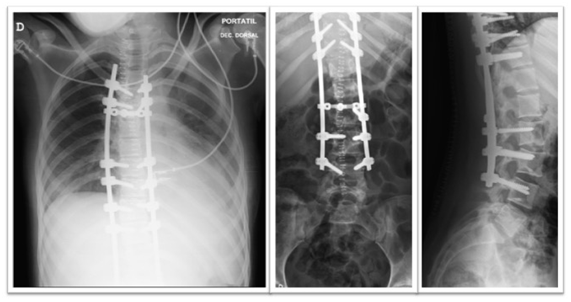

A chest tube was inserted with immediate drainage of 800 mL of blood. During the following 12 hours, 100 mL more were drained. Another CT scan was performed in order to confirm the position of the chest tube. All the clinical and analytical manifestations were solved after the chest tube insertion (Figure 3&4).